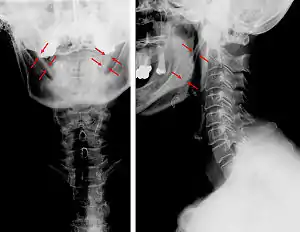

![]() | |

| Anteroposterior and lateral radiographs of cervical spine showing ossification of the stylohyoid ligament on both sides | |